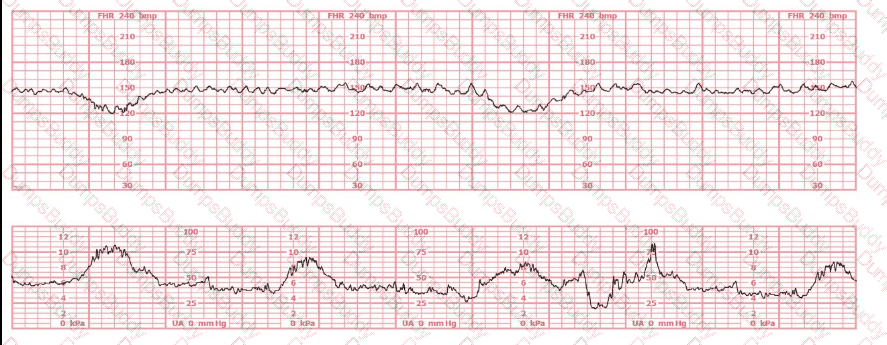

The decelerations seen in the fetal monitoring tracing shown are best described as: